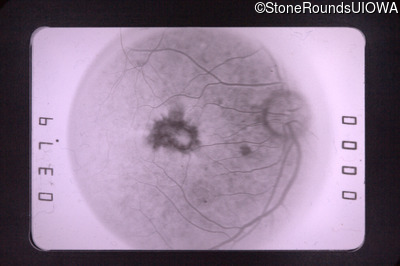

Fluorescein Angiography - Right - 20/70

Exemplar